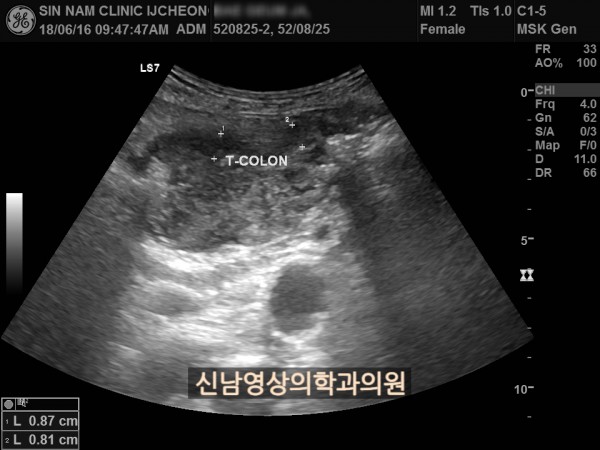

본 환자분은 변비가 지속되면서 좌하복부 통증이 있으셨던 분으로 본원에서 복부 초음파 검사를 진행하였습니다.

하행 결장 부위에서 장이 두꺼워진 소견이 보여 진행된 대장암의 가능성이 농후해보여 대학병원으로 전원해 대장내시경을 받고, 수술로 2기암으로 진단되신 케이스입니다.

위암이나 대장암은 점막에서 발생하는 0기암은 초음파로 진단할 수 없지만 대장암이 점막을 넘어 근육층이나 장간막으로 퍼지게 되면 초음파 검사상 근육, 장간막 부위가 두꺼워지는 소견으로 나타나 발견하기도 합니다.